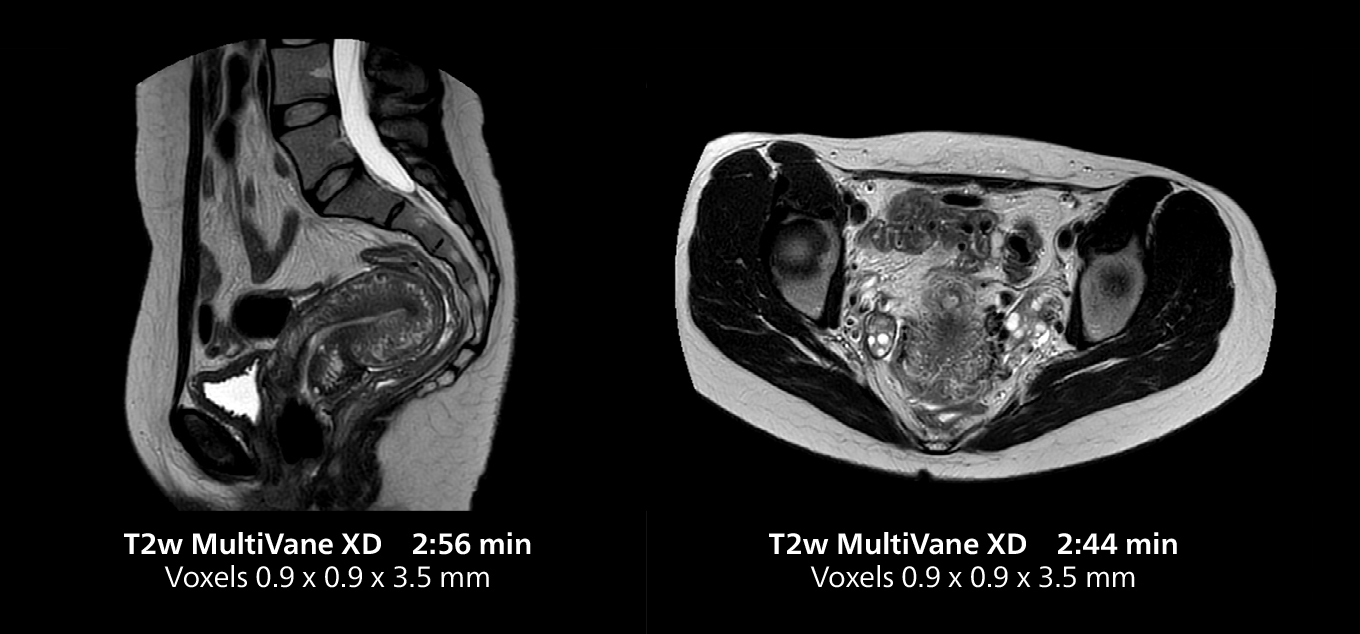

Le Dr Gellée estime que la fiabilité des acquisitions en respiration libre est “la caractéristique qui fait la plus grande différence au quotidien. Les séquences 3D en respiration libre sont très reproductibles et l’acquisition axiale est très bonne. Par exemple, pour l’endométriose, qui est l’un de mes domaines de prédilection, elles offrent un contraste élevé et une bonne résolution, ce qui me permet de voir les moindres détails. Nous utilisons également la respiration libre pour l’imagerie du foie et du pancréas. Dans les examens du foie multiphases, la respiration libre 4D offre une résolution temporelle de 3 secondes, permettant une acquisition dynamique avec plusieurs phases artérielles.”

Pour les patients âgés en particulier, les protocoles de respiration libre rendent les examens plus confortables tout en assurant la qualité d’image nécessaire à un diagnostic efficace. “Il y a un grand nombre de personnes âgées dans la ville, et puisqu’il est souvent difficile pour elles de retenir leur souffle, la respiration libre est un avantage significatif”, explique le Dr Gellée. “Pour l’IRM cardiaque par exemple, avec le 4D Flow et les réhaussements tardifs, nous obtenons une excellente qualité diagnostique sans demander à nos patients de retenir leur respiration.”

Le système MR 5300 doté de Compressed SENSE est jusqu’à 50 %** plus rapide pour de nombreux examens. Il permet de réaliser des examens de routine en moins de 5 minutes et des examens du corps entier en moins de 20 minutes. Saint-Augustin a su profiter de cette rapidité pour créer des protocoles très efficaces. La procédure d’AVC standard de l’hôpital ne dure qu’environ 8 minutes, et les examens ORL standard, la classification PIRADS de la prostate et les examens de l’endométriose ne durent tous qu’environ 10 minutes***.